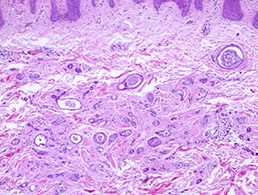

조직학적 사진 보시면 여드름과 다르게 표피 바로 밑에 주머니가 있고 주머니 안에 각질이 차 있기 때문입니다.

한관종은 땀관종이라고도 불리고, 땀샘관 조직이 비정상적으로 늘어나서 생긴 양성 종양으로 조직학 사진에서 보는 바와 같이 관처럼 보이는 조직이 보입니다.